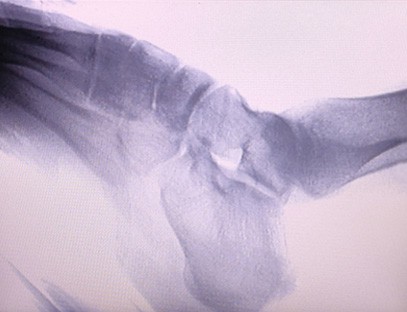

Is táirge ardchaighdeáin é ár Meaisín X-gha Ortaipéideach a dearadh go háirithe le haghaidh íomháithe ortaipéideacha. Is féidir é a úsáid le haghaidh diagnóis agus pleanáil cóireála ar choinníollacha ortaipéideacha éagsúla, lena n-áirítear bristeacha, dislocations, airtríteas, agus siadaí cnámh. Tá sé feistithe le teicneolaíocht X-gha chun cinn a chuireann ar chumas íomhánna ardcháilíochta le nochtadh radaíochta laghdaithe. Tá córas íomháithe ardtaifigh ag an meaisín agus is féidir íomhánna d'aon struchtúr cnámh a ghabháil le soiléireacht mhór.

Is féidir ár Meaisín X-gha Ortaipéideach a úsáid i speisialtachtaí leighis éagsúla, lena n-áirítear ortaipéidic, néareolaíocht agus leigheas éigeandála. Is minic a úsáidtear é chun breathnú fluarascópach ar chnámha géaga daonna, ospidéil Tréidliachta agus peataí, Cóireáil créachtaithe ag láithreáin spóirt, foirgnimh, longa farraige, limistéir iargúlta agus láithreáin pháirce míleata. I measc cuid de na hiarratais chliniciúla tá:

1. Diagnóis bristeacha, dislocations, agus gortuithe cnámh eile.

2. Meastóireacht ar ghalair chomhpháirteacha mar airtríteas, galar degenerative comhpháirteach, agus oistéapóróis.

4. Pleanáil réamhoibríoch do lialanna ortaipéideacha.